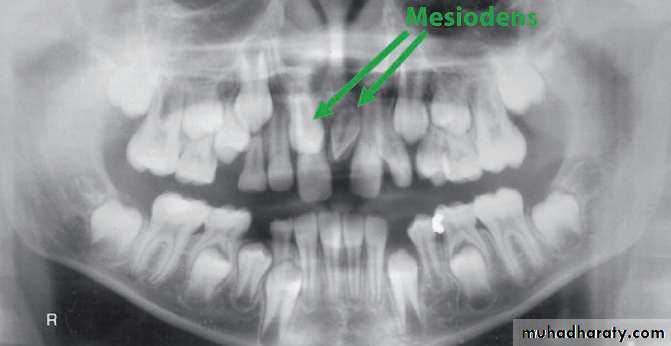

• Mesiodens :When they occur between the maxillary central incisors.

Parateeth(paramolar): Those occurring in the molar area .

Distodens or distomolar : Those that erupt distal to the third

molar.

Paramolar blocking the eruption of 3rd molar.

MesiodensDistomolars(4th molar)

Mesiodens

Distodens or distomolarParamolar

Many supernumerary teeth never erupt, but they may delay eruption of nearby teeth or cause other dental problems.